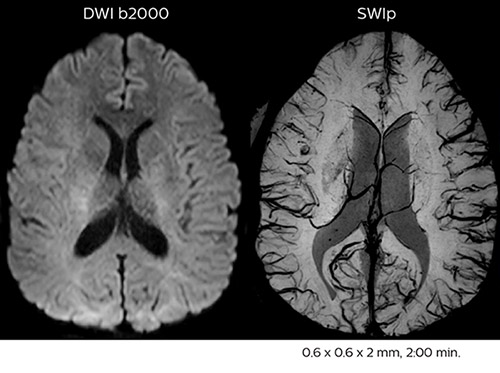

Fast acute stroke protocol

This is an example of acute ischemic stroke with distal occlusion of the right posterior cerebral artery. Note the improved visibility of the ischemic territory on the diffusion weighted image with high b-value. The 3D FLAIR shows a distal PCA occlusion. The fast SWIp depicts the thrombus on the isolated second echo image. The total scan time (including SmartBrain, preparations and a fast 3D T1w TSE Gd) is 8:00 minutes.

Acute right motor deficit and aphasia

In this patient with acute right motor deficit and aphasia, the b2000 diffusion weighted image is normal. The SWIp image demonstrates more prominent veins in the right hemisphere, which could reflect increased deoxyhemoglobin contents. Fast ASL shows low CBF regions in the left frontal lobe. A follow-up ASL after one hour demonstrates high CBF values in the same area. The final diagnosis was migraine with aura.